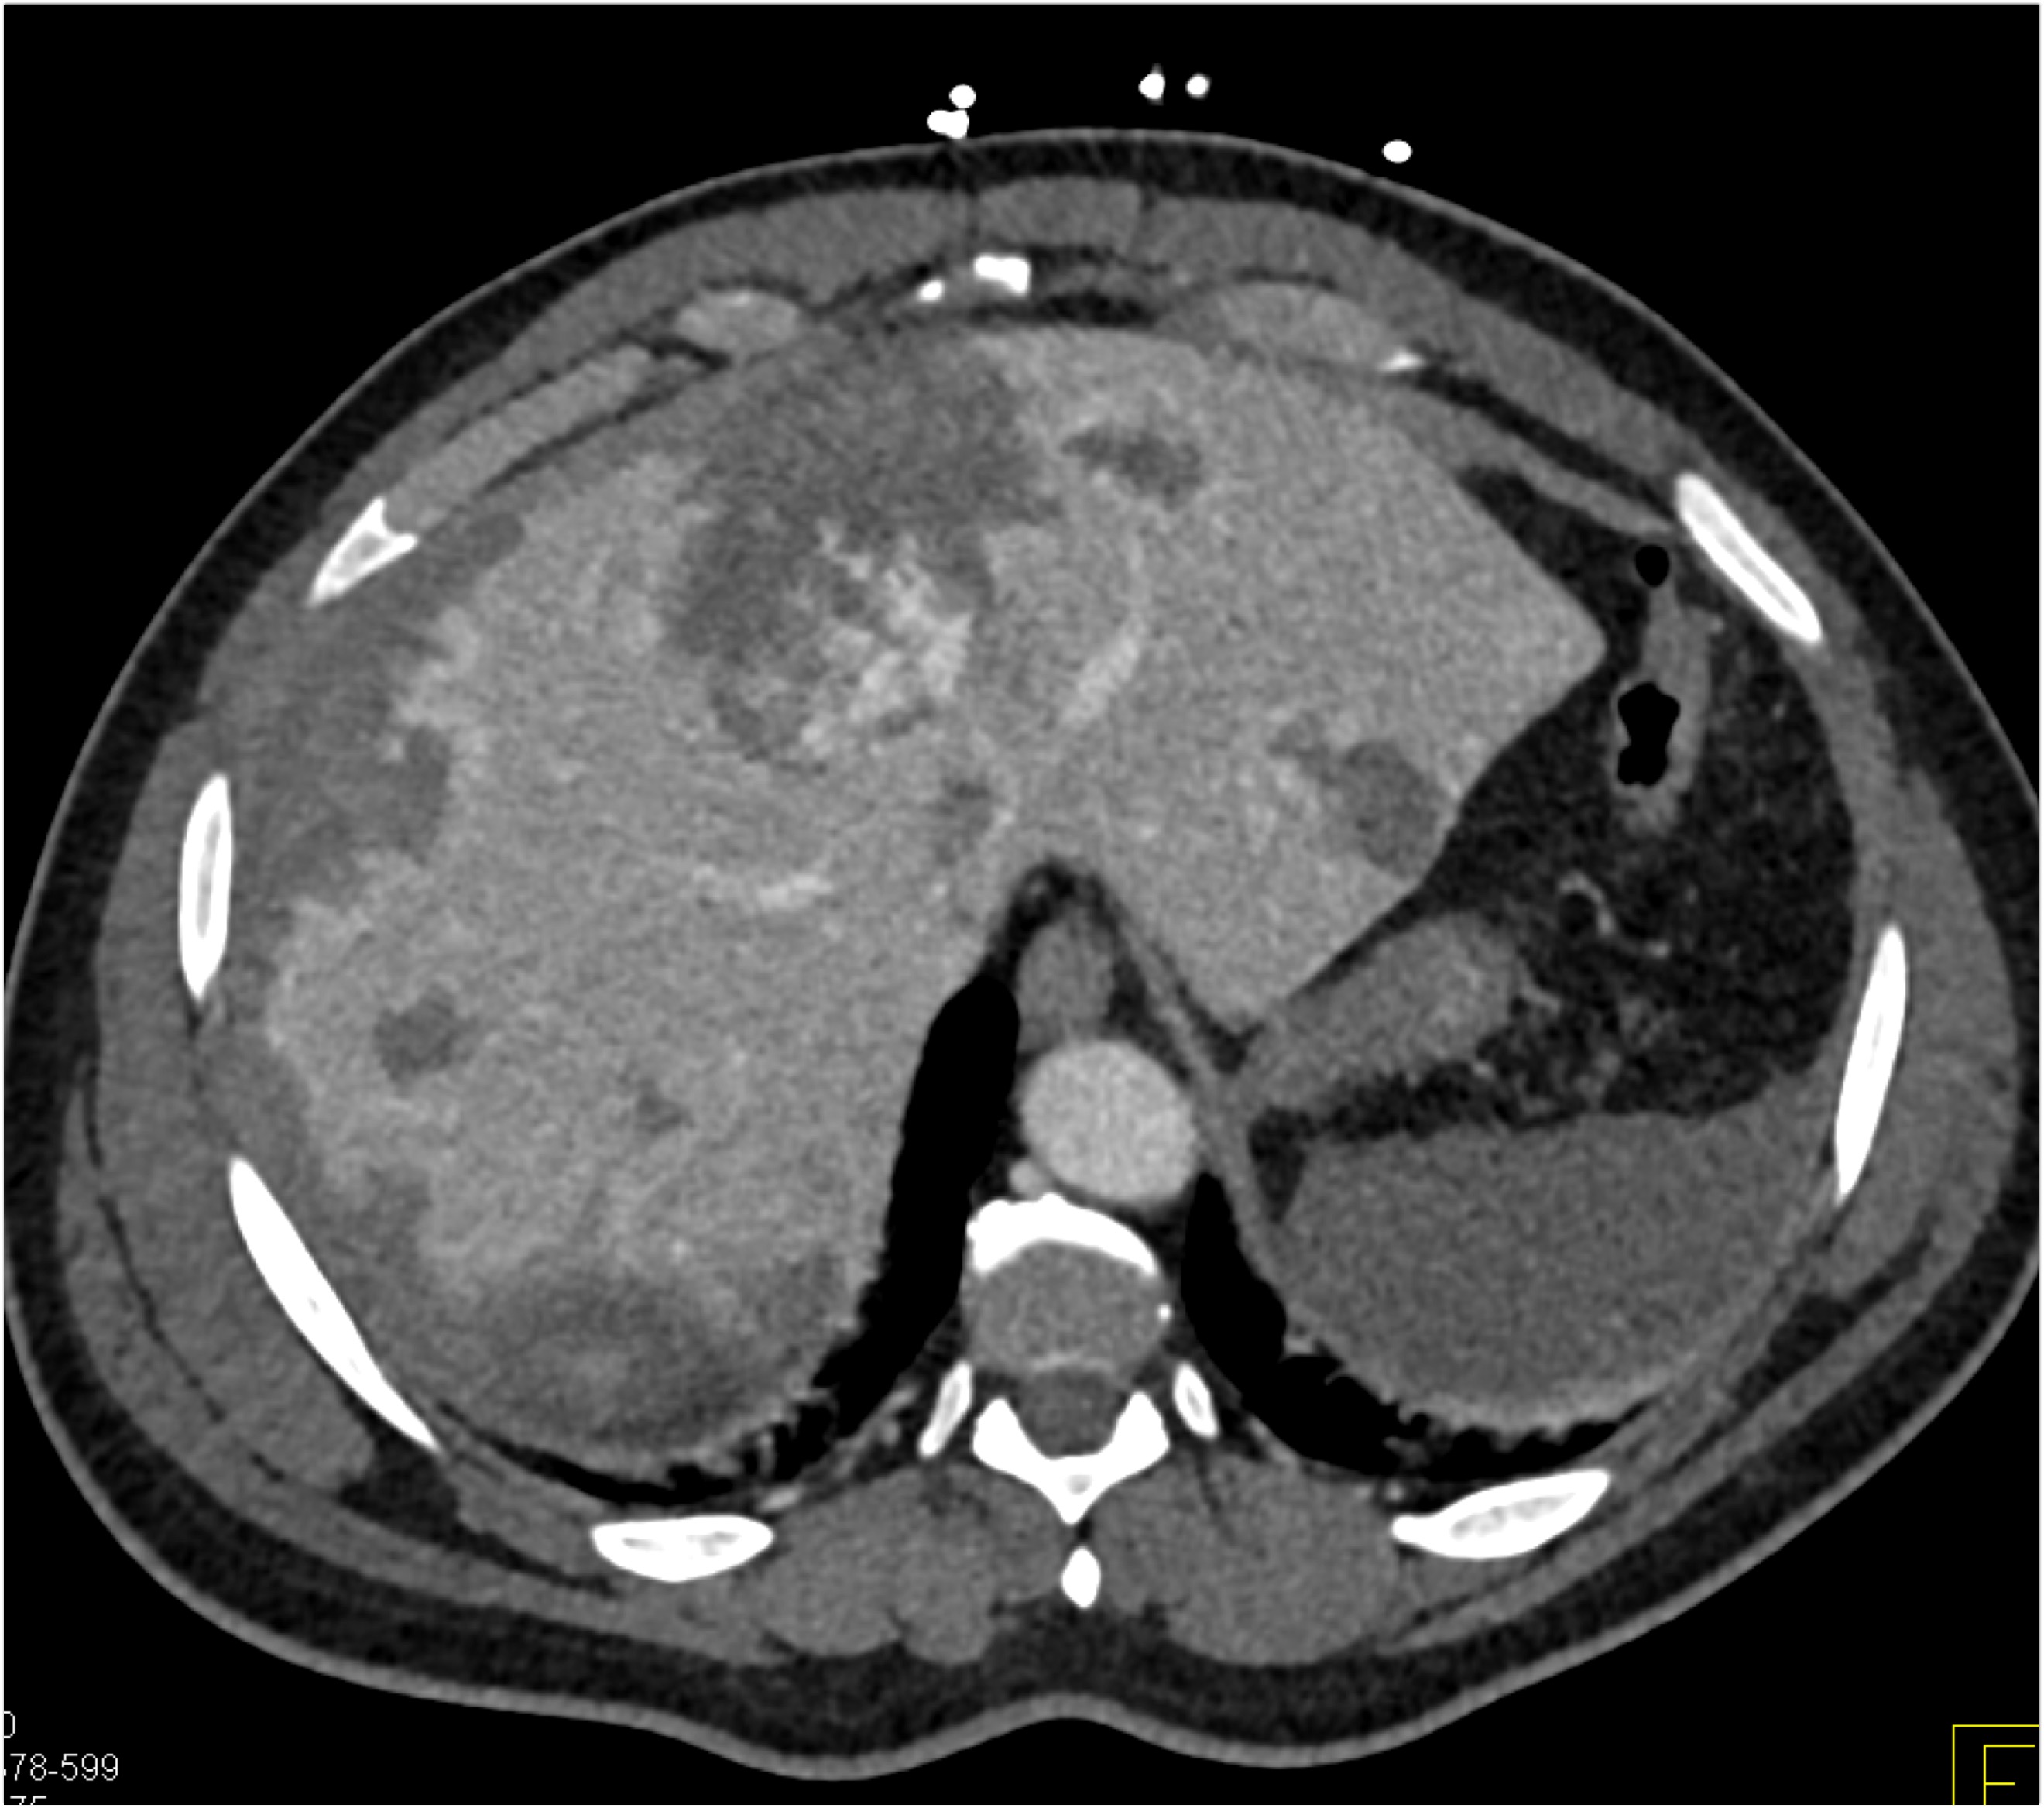

8) The most likely diagnosis in this case is?

clear cell renal cell carcinoma

large B-cell lymphoma

seminoma

renal abscess